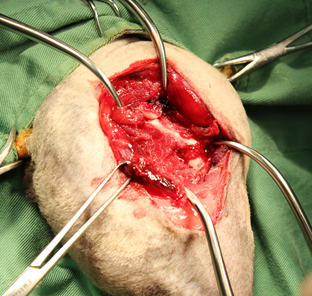

症例:去勢雄 1歳6ヶ月 雑種猫

主訴:右後肢を完全に着かないとのことでかかりつけの病院を受診、レントゲン検査にて右後肢大腿骨の完全粉砕骨折と診断され、当病院を紹介され来院されました。 当病院のレントゲン検査でも右大腿骨粉砕骨折が確認されたため、飼い主様にプレートによる固定手術をおすすめし、希望されたため手術行いました。

骨片が5つ以上あり、複雑骨折と診断

リコンストラクションプレート、ラグスクリューを使用し固定しました。